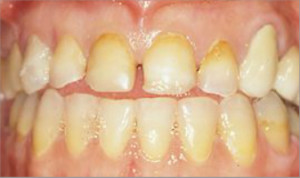

Rehabilitación completa, fundas de porcelana y tratamiento periodontal